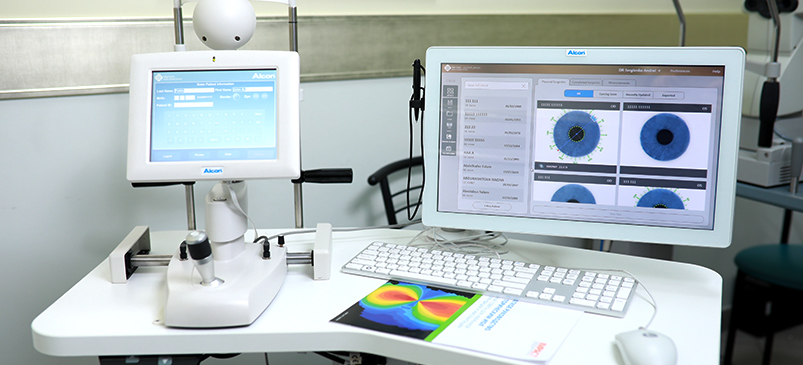

Рефракційна хірургія

Ексімер-лазерна корекція (ЕЛК) з усіма існуючими методами: LASIK, PRK, LASEK, Epi-LASIK, Cool-LASIK.

Найкраще обладнання

Наша клініка оснащена обладнанням від провідних виробників Японії, США і Європи. Завдяки цьому здійснюється найбільш точне діагностування, значить і можливе подальше якісне лікування з досягненням високих показників.